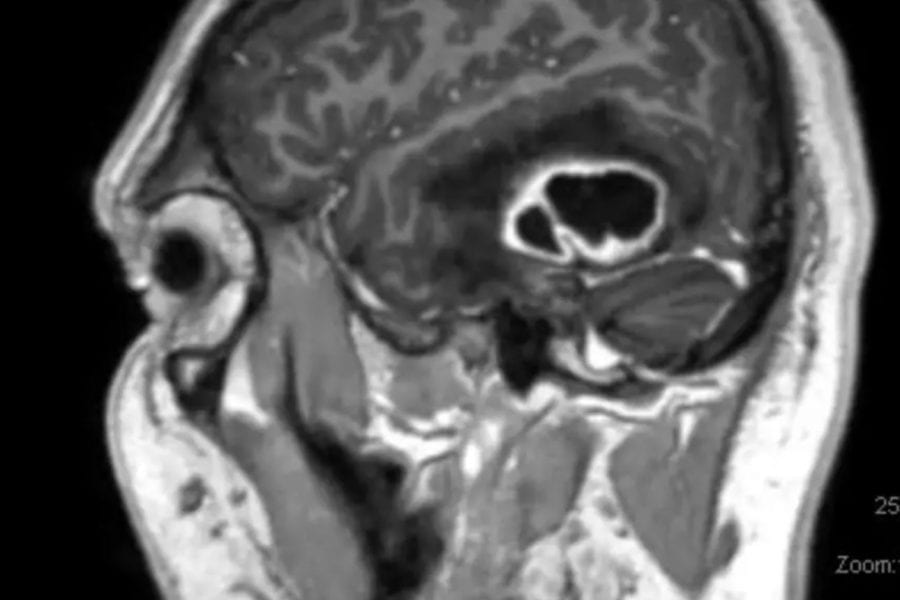

Introduction 30% of the population will develop significant neck pain. The pain is usually due to a disc herniation. If the disc protrusion is small pain tends to…